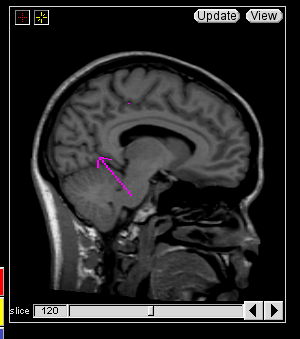

Trace the Central Sulcus in the sagittal view. Select a medial sagittal slice where the “dots” from the sulci lines drawn in the axial view are visible. Trace this sulcus inferiorly to the corpus collosum (Fig 7-8).

Figure 7                  Figure

8